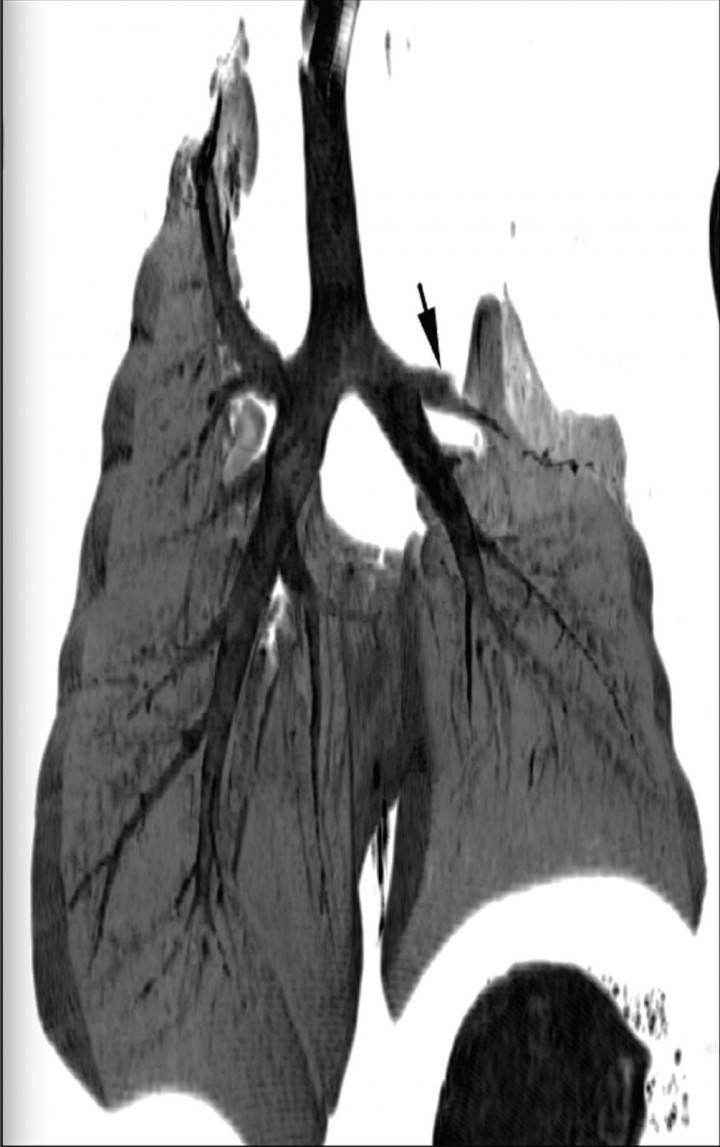

Como prueba definitiva de diagnóstico se recurrió a la tomografía computarizada (TC), en la que se observó una terminación abrupta del bronquio principal de la porción craneal del lóbulo pulmonar craneal izquierdo, confirmando así la sospecha de torsión (Fig. 4). El lóbulo afectado presentaba atelectasia severa y un árbol bronquial dilatado y relleno de líquido (Fig. 5). Tras la administración de contraste intravenoso no se observaron venas y arterias pulmonares normales porque, al igual que el bronquio, terminaban abruptamente a nivel del hilio. Asimismo, la distribución periférica de contraste y el realce pleural sugerían la presencia de pleuritis, adherencias y necrosis pulmonar, indicando que los cambios eran muy crónicos, lo que podría complicar la cirugía.

<p>Reconstrucción multiplanar dorsal de mínima intensidad (minIP). La flecha negra señala la terminación abrupta de la porción craneal del bronquio principal del lóbulo pulmonar craneal izquierdo.</p>

Reconstrucción multiplanar dorsal de mínima intensidad (minIP). La flecha negra señala la terminación abrupta de la porción craneal del bronquio principal del lóbulo pulmonar craneal izquierdo.